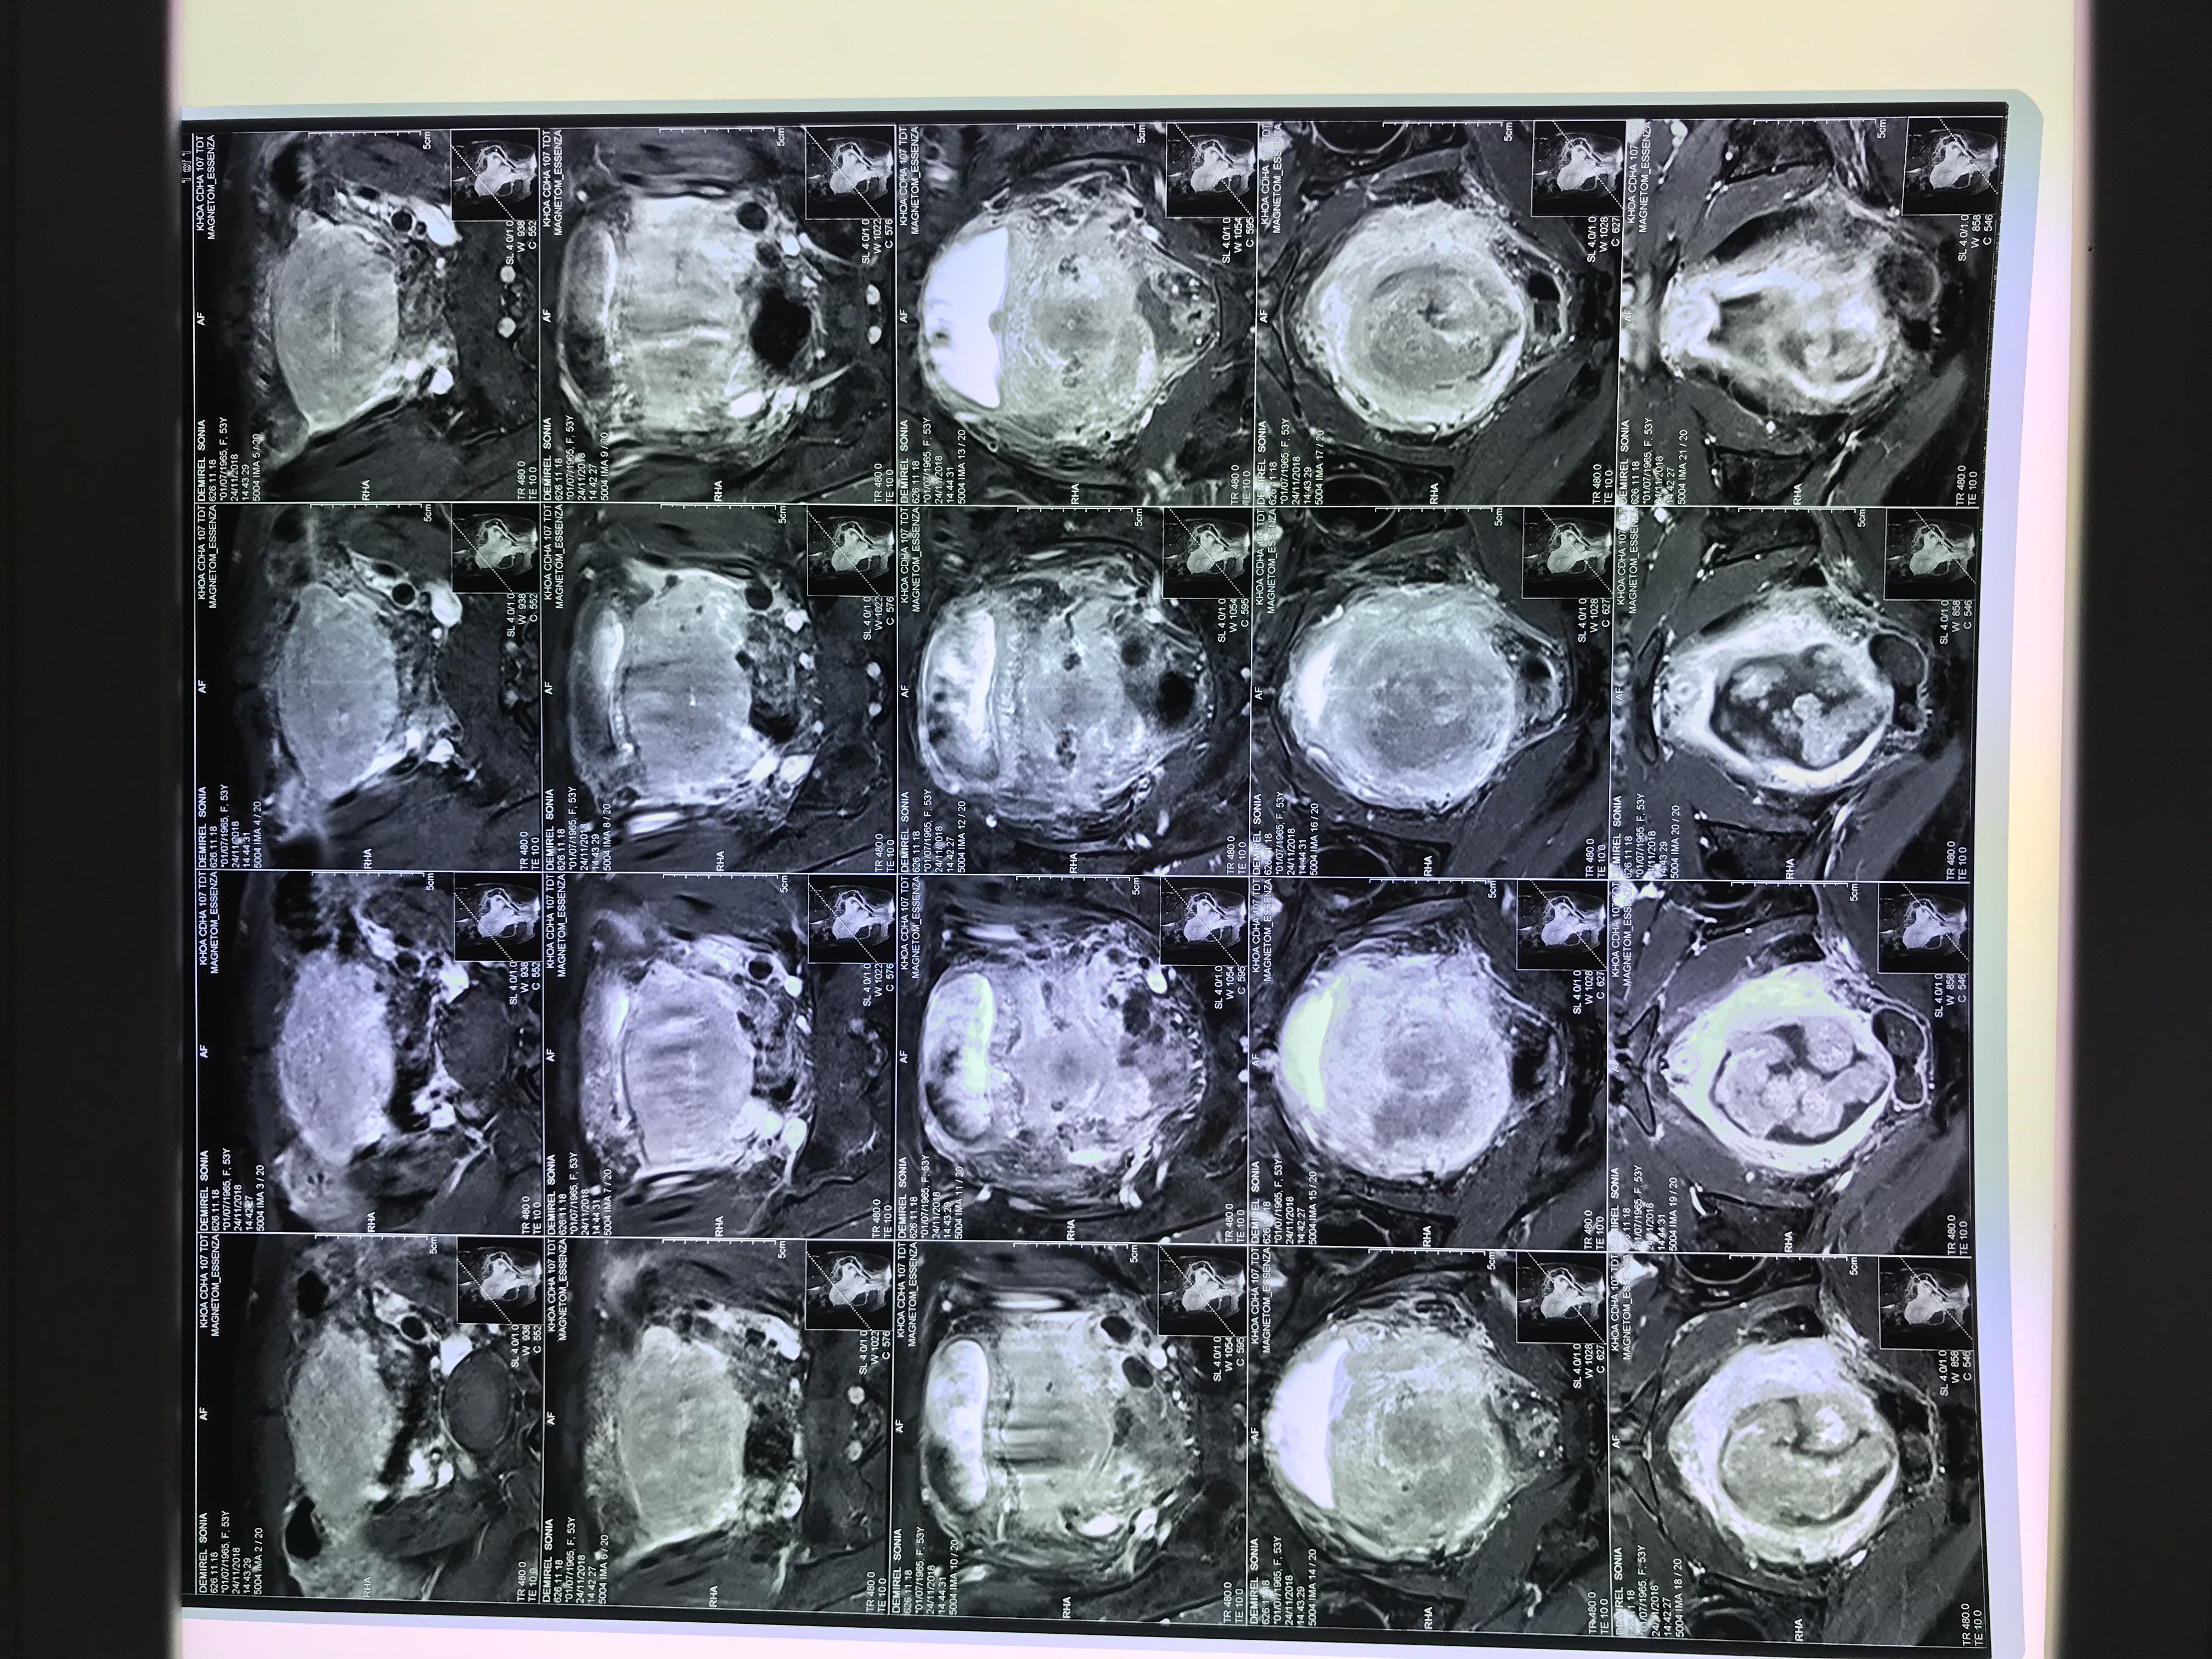

Hình ảnh khối u xâm lấn trên bệnh nhân S. Ảnh: VGP/Trần Hà

Mới đây, khoa Hồi sức cấp cứu, Bệnh viện K đã tiếp nhận trường hợp nữ bệnh nhân S. (54 tuổi), chẩn đoán ung thư cổ tử cung, nhập viện trong tình trạng ra máu âm đạo, chóng mặt, buồn nôn, da xanh niêm mạc nhợt, vô niệu.

Xét nghiệm cho thấy, bệnh nhân bị suy thận cấp do khối ung thư cổ tử cung xâm lấn lan rộng. Các bác sĩ đã truyền máu, lọc máu, cấp cứu tích cực cho bệnh nhân. Bệnh nhân được chẩn đoán bị suy thận cấp và mắc ung thư cổ tử cung giai đoạn IV, sẽ tiếp tục được theo dõi và điều trị theo phác đồ.